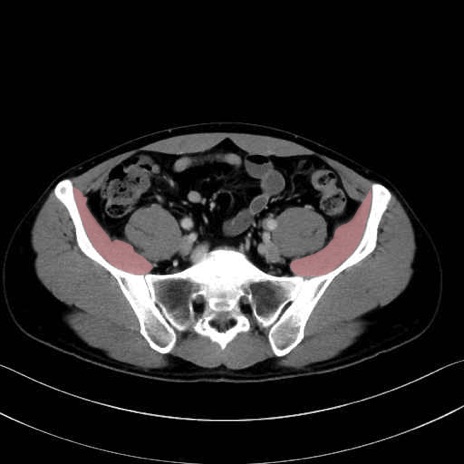

大腰筋 (Psoas major)

腸骨筋 (Iliacus)